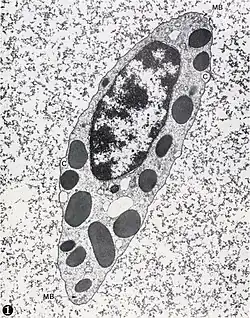

У взрослого человека лимфоциты составляют 20—35 % всех лейкоцитов. По размеру лимфоциты подразделяют на малые (диаметром 4,5—6 мкм), средние (диаметром 7—10 мкм) и большие (диаметром 10 мкм и более). Большие лимфоциты присутствуют только у новорождённых и детей, у взрослых 85—90 % составляют малые лимфоциты. Лимфоциты имеют интенсивно окрашенное округлое или бобовидное ядро и относительно узкую прослойку базофильной цитоплазмы[18].